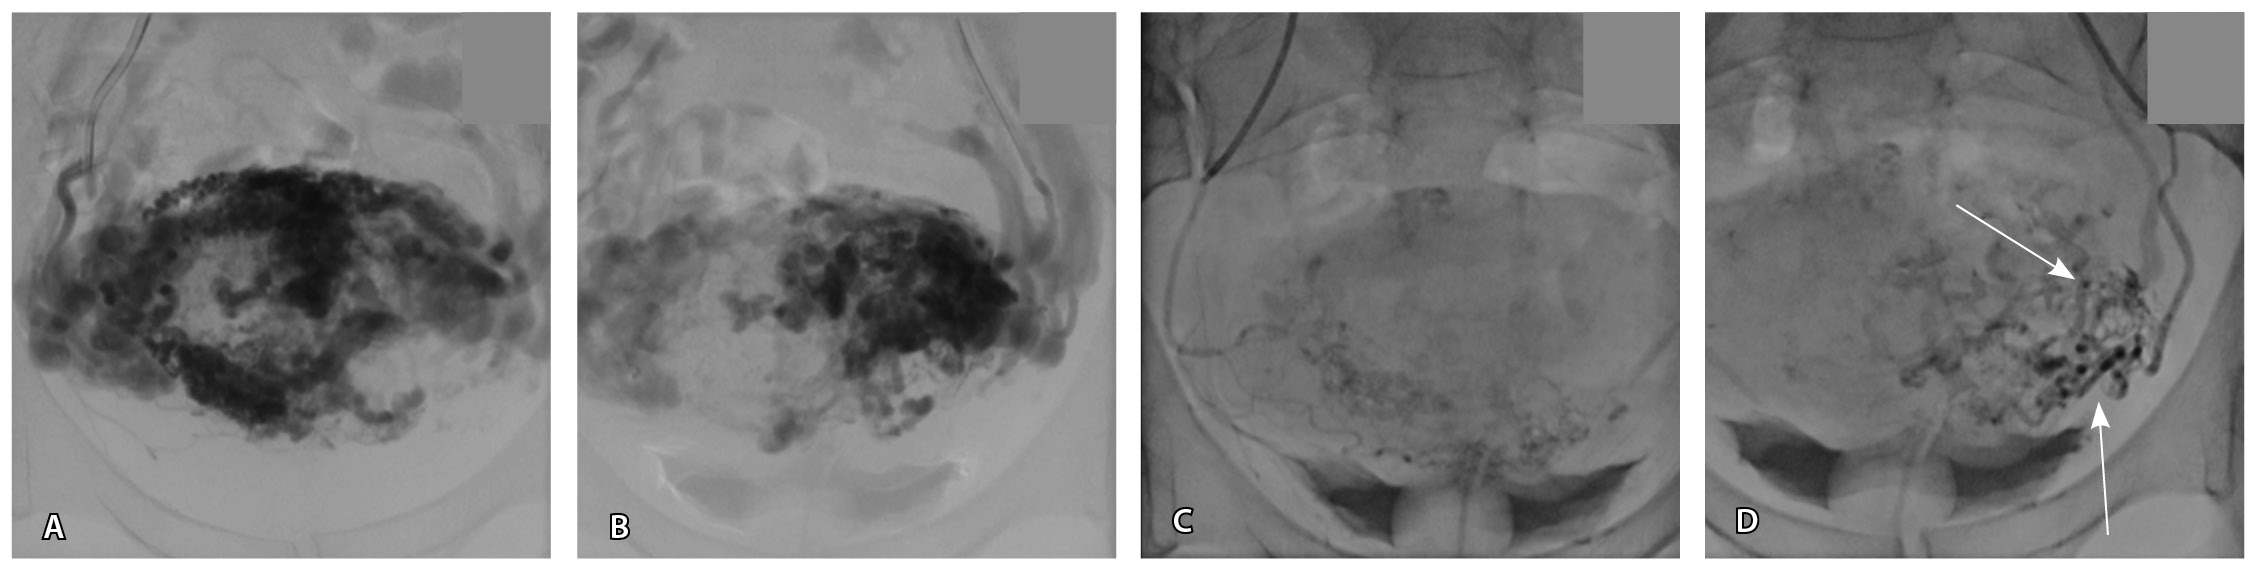

Исходя из клинической и визуальной картины, пациентке выполнено оперативное лечение. Первым этапом проведена эмболизация маточных артерий. Под местной анестезией раствором ропивакаина пунктирована правая лучевая артерия. Установлен интродьюсер 5F. Катетером НН последовательно катетеризированы левая и правая внутренние подвздошные артерии, выполнена ангиография. На ангиограммах: артериовенозная мальформация в проекции матки; афферентные артерии – маточные и цервиковагинальные – с обеих сторон, две ветви 1 мм в диаметре от левой внутренней подвздошной артерии; эфферентные сосуды – вены параметрия, внутренние подвздошные вены и яичниковые вены с обеих сторон (рис. 4).

Рис. 4. Данные рентгеноконтрастной ангиографии. А, Б – ангиограммы бассейнов правой и левой маточных артерий. Зоны патологической васкуляризации в проекции тела матки: массивная сеть измененных артерий и вен, ранний артериовенозный сброс в вены параметрия, внутренние подвздошные вены и яичниковые вены с обеих сторон. В, Г – ангиограммы бассейнов правой и левой цервиковагинальных артерий. Контрастирование зоны патологической васкуляризации в проекции шейки и нижнего отдела тела матки, ранний артериовенозный сброс в вены параметрия преимущественно слева и в левую внутреннюю подвздошную вену (стрелки)

Выполнена эмболизация маточных и цервиковагинальных артерий с обеих сторон материалом PVA (1000 мкм) и эмболами из гемостатической губки. На контрольных ангиограммах патологическое сосудистое сплетение не контрастируется, артериовенозный сброс устранен (рис. 5). Катетеры и интродьюсер удалены, выполнен компрессионный гемостаз, наложена асептическая давящая повязка. Контрастный препарат йодиксанол (320 мг йода/мл) – 300 мл. Эффективная доза – 1,8 мЗв.

Рис. 5. Контрольные снимки после эмболизации маточных и цервиковагинальных артерий. Ангиограммы бассейнов правой и левой внутренних подвздошных артерий. Правая маточная и цервиковагинальная артерии, а также патологическое сосудистое сплетение в их бассейне не контрастируются, ранний артериовенозный сброс устранен. Незначительное контрастирование сегмента патологической сети по единичной мелкой ветви внутренней подвздошной артерии справа, по двум мелким ветвям внутренней подвздошной артерии слева (указано стрелками)